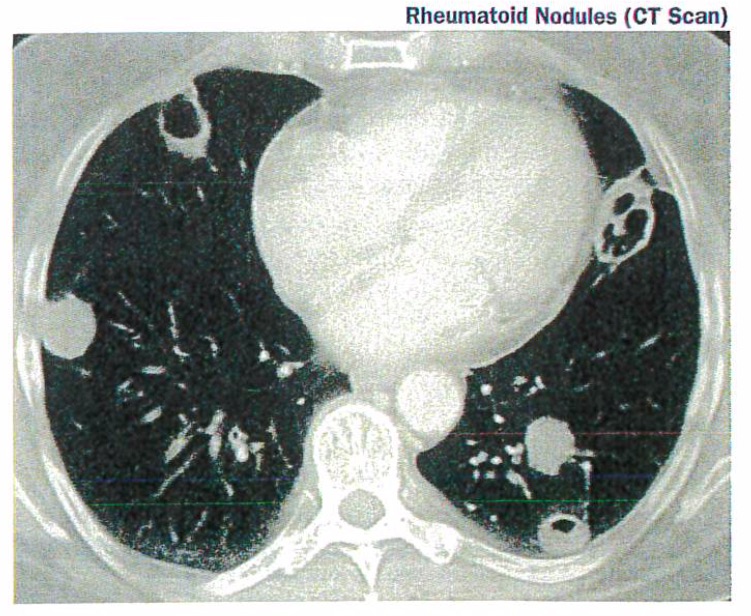

Pulmonary Manifestations of Rheumatoid Arthritis Doctorpedia Arthritis In Nodules About 25% of people with rheumatoid arthritis develop firm lumps under the skin called rheumatoid nodules. Rheumatoid nodules are firm lumps under the skin. They tend to form close to joints in people affected by rheumatoid arthritis. Rheumatoid nodules are firm, noticeable lumps that form underneath the skin of some. They appear on fingers, knuckles, elbows, forearms, and knees. The. Arthritis In Nodules.